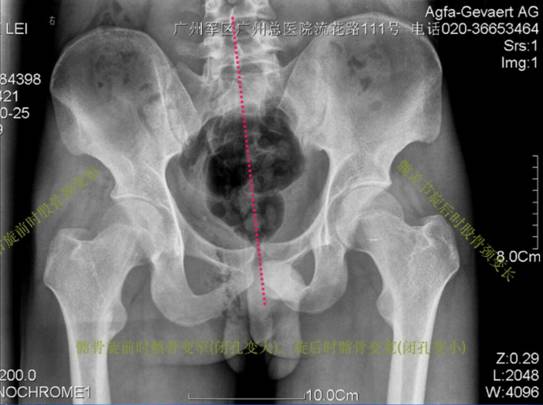

X线片

通过片子也能发现骨盆偏歪的问题。即使大家不懂医学,但看看骨盆下面两个像眼睛一样的圆洞洞,是不是不一样大,髋骨两边像耳朵一样的骨头是不是不一样大,骨头最上缘是不是不在一条直线上,片子可以清晰地显示出来。